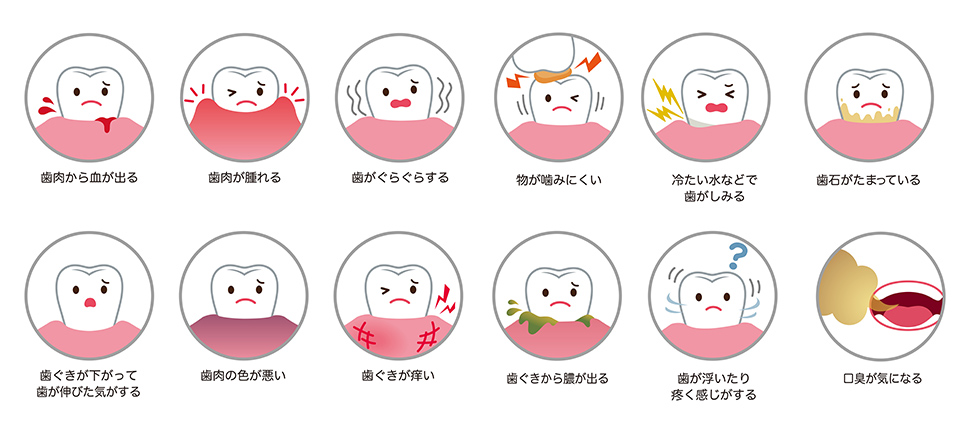

初期段階では自覚症状はほとんどなく、「歯周病かも」とご自身で気付いた時には、かなり進行した状態になっていることも少なくありません。

気になる症状がある方は早めに当院にご相談ください。

この中で1つでも症状が当てはまる方はお早めに検査にお越しください。